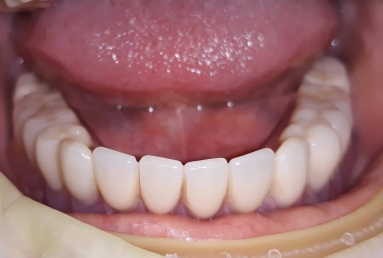

Female patient with advanced periodontal disease has mobility of all teeth and old dental work. All mandibular teeth were extracted and replaced with 4 dental implants ( Alpha bio Nobel).

The mobile prosthesis is fixed with 4 locators that firmly stabilise it. The mastication, talking and aesthetics is very comfortably and safely obtained.